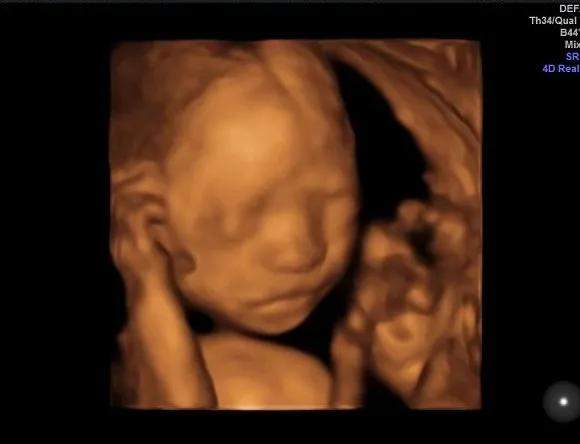

嗯,开始检查了!医生在妈妈肚子上涂了好多凉凉的东西,然后用一个小仪器在妈妈的肚子上探来探去。没多久,妈妈就看到了你的动态了哦!妈妈真的像在四维影院看电影一样的,看到你在肚子里各种欢腾的样子。

你看你爸爸,激动的一直说话,“老婆老婆!你看宝宝鼻梁多高,你看他还在吃手,你看他圆圆的脑袋好可爱啊……”宝贝,你爸爸是不是像个大孩子一样,看到你就手舞足蹈,语无伦次了。哈哈哈哈,你老爸让你一定要遗传他那活泼又搞笑的基因呢!

嘿嘿,下面照片就是你的“写真”,还是“裸体”的呢,不要害羞哈!这个可是爸爸妈妈送给你的礼物哦。等你长大了,看到在妈妈肚子里面的照片,是不是会很意外啊?嘿嘿,这个啊就是四维彩超的神奇功效啦,可以让爸爸妈妈看到你健健康康的成长,看到你欢快的动作还让爸爸妈妈稀里哗啦的留下了好多感动的眼泪呢。宝宝,爸爸妈妈等着你哦!

(转过来转过去,只为让医生和粑粑麻麻更清楚的看到我的盛世美颜)